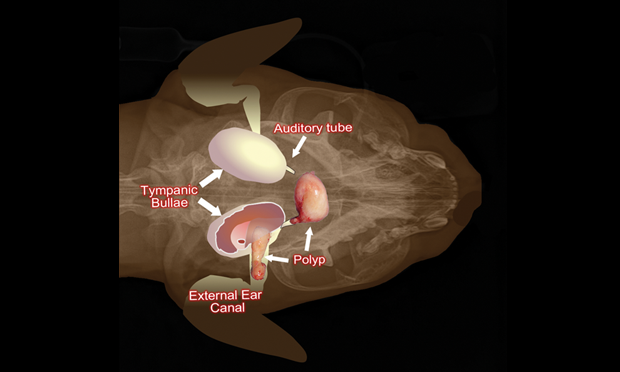

How to Diagnose and Treat Aural Polyps in Cats 11 Steps online, How to Diagnose and Treat Aural Polyps in Cats 11 Steps online, How to Diagnose and Treat Aural Polyps in Cats 11 Steps online, Ear Polyps in Cats PetCoach online, Ear Infections in Dogs Cats Natural Treatment and Prevention online, How to Diagnose and Treat Aural Polyps in Cats 11 Steps online, Cat Ear Infection Home Remedies Real Results online, Surgical Removal of Feline Inflammatory Polyps online, Hardwick Veterinary Nasopharyngeal Polyps in Cats online, Cat Ear Infections PetMD online, Helping the homeless Charlotte s delicate middle ear surgery online, What Are Cat Polyps And Should You Be Concerned GoodRx online, How To Tell If Your Cat Has an Ear Infection and What to Do online, 7 Reasons Your Pet Has Chronic Ear Infections Vet In Palm City online, Ear Polyps in Cats Causes Signs Care Vet Answer Catster online, Nasopharyngeal Polyps in Animals Ear Disorders MSD Veterinary online, Are these grey globules attached to my cat s ears some kind of online, What Are Cat Polyps And Should You Be Concerned GoodRx online, Inflammatory Ear Polyps in Cats BluePearl Pet Hospital online, Inflammatory Ear Polyps in Cats What s the Prognosis online, How to Diagnose and Treat Aural Polyps in Cats 11 Steps online, Ear Tumor Surgery Needed for my Zoe GoFundMe Campaign Chicago online, Cat Ear Infections 8 Steps for Treating Them at Home PetMD online, Surgery on ear polyps will make cat feel better Boston Herald online, Ear Infections in Cats Causes Signs Care Tips Catster online, The Best Home Remedies for Ear Mites in Cats Easy Tips online, Nasopharyngeal Polyps in Cats Tufts Catnip online, How to Diagnose and Treat Aural Polyps in Cats 11 Steps online, Ask the Vet Inflammatory polyps may be to blame for feline ear online, GUYS HELP I found this thing in my cats ear today and I don t online, Ear Tumors online, Inner Ear Infection in Cats Los Angeles Vet online, Middle Ear Aural Polyp Extraction online, Wired for Sound Cool Facts About Cat Ear Anatomy Fear Free online, Animal Surgical Center of Michigan Veterinarian in Flint MI online, Cat Ear Infection Home Remedies Real Results online, When Ear Infections Deepen Catwatch Newsletter online, Ear Scratching and Headshaking Catwatch Newsletter online, Ear Infections in Cats Small Door Veterinary online, Ear polyps in the ear of a cat. Removal under anesthesia by a veterinarian online, Cat Ear Yeast Infection Treatment Banixx online, Ear Cancer online, Nasopharyngeal Polyps in Cats Causes Symptoms and Treatment online, Cat owners Beware of polyps The River Reporter online, Nasal Polyps In Cats Symptoms And Treatment Options Kingsdale online, Ear infections in cats PDSA online, Ear Infections in Cats Effective NATURAL Remedies Dr. Katie Woodley The Natural Pet Doctor online, Cat Ear Hematoma PetMD online, Ear Problems in Cats International Cat Care online, Ear Polyps in Cats online.

Cat ear polyp home remedy online